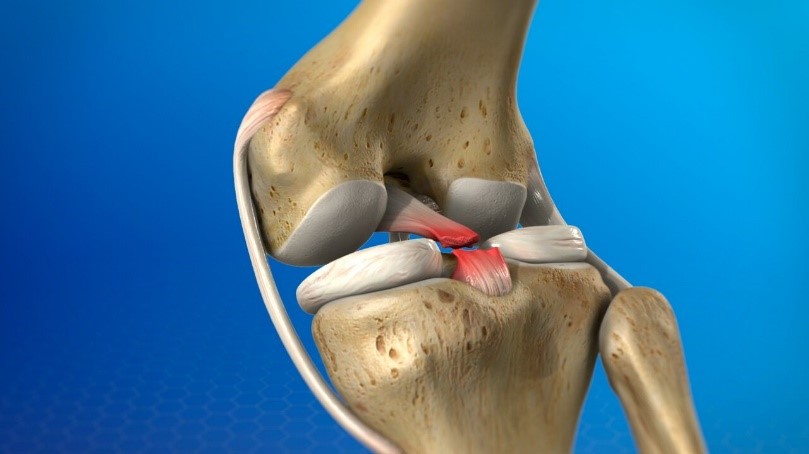

The posterior cruciate ligament (PCL) is located in the knee, just behind the anterior cruciate ligament (ACL). It is one of the ligaments that connects the shinbone (tibia) to the thighbone (femur). The posterior cruciate ligament restricts the tibia from moving backward with respect to the femur.

PCL tears result in knee instability. PCL tears are less common than ACL tears.